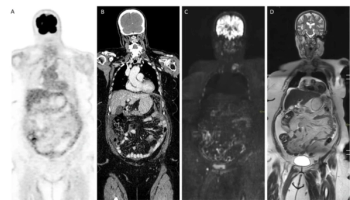

In newly published guidelines, researchers discuss the utility of CT, MRI and PET/CT in the diagnosis, staging, treatment monitoring and follow-up imaging for peritoneal metastases in patients with ovarian or colorectal cancer.